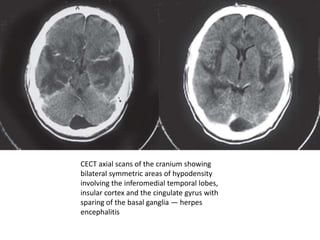

CECT axial scans of the cranium showing

bilateral symmetric areas of hypodensity

involving the inferomedial temporal lobes,

insular cortex and the cingulate gyrus with

sparing of the basal ganglia — herpes

encephalitis

• CT scan may demonstrate hypodense

temporal lobe lesions with or without

involvement of the frontal lobes

• hemorrhagic temporal lobe lesions in the

appropriate clinical setting are highly

suggestive of HSV-1 encephalitis,

• Contrast Enhanced CT scans show streaky

linear enhancement in the region of the

sylvian fissure and the island of Reil.

• MR imaging can demonstrate the early edematous changes

of herpes encephalitis seen as hypointensity on T1 and

hyperintensity on T2-weighted images with characteristic

involvement of the temporal lobes and inferior frontal

lobes.

• Fluid attenuated inversion-recovery (FLAIR) imaging is even

more sensitive than T2-weighted images

• Diffusion weighted imaging (DWI) shows increased signal in

the affected areas to a greater extent than do the T2-

weighted and FLAIR sequences.

• Early on in the disease process, contrast enhancement is

absent but gyriform enhancement occurs with disease

progression.